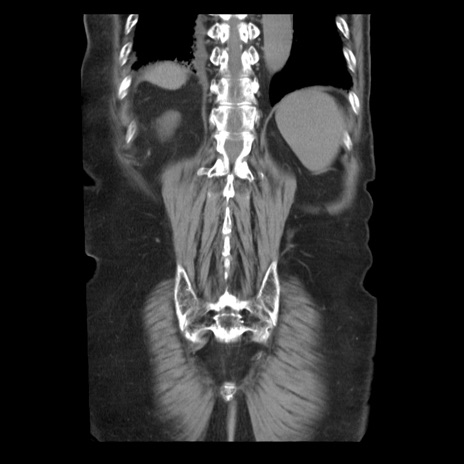

症例21(冠状断像)

【症例】70歳代男性

【主訴】腹痛

【現病歴】肝硬変・肝細胞癌にてかかりつけの方。約9時間前に食後より腹痛出現。症状が徐々に増悪し、嘔吐出現したため来院。

【既往歴】肝硬変、肝細胞癌(RFA、TACE後)

【身体所見】意識清明、表情苦悶様、BT 36℃、BP 129/78mmHg、P 88bpm、SpO2 97%(RA)、右上腹部から心窩部にかけて圧痛あり、反跳痛なし、筋性防御あり。

【データ】WBC 5800、CRP 0.16